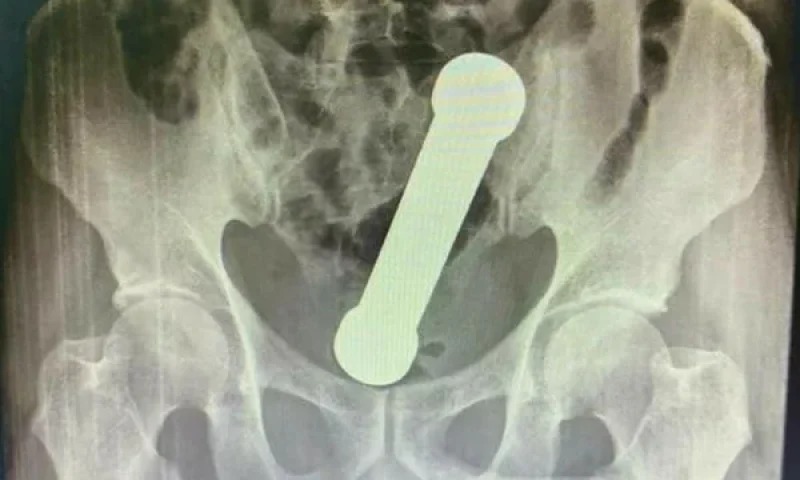

Manaus/AM - Um homem de 54 teve que ser operado em Manaus, após um exame de raio-X detectar a existência de um peso de academia em seu corpo.

Segundo a publicação, o homem procurou uma unidade de saúde da capital amazonense sentido há dois dias fortes dores, náuseas e dificuldade de evacuação. O peso tinha aproximadamente 2 quilos e cerca de 20 centímetros de comprimento.

O haltere estava entre o reto e o intestino grosso do paciente, que, após a surpresa da equipe médica, admitiu ter introduzido o peso de academia no corpo para obter satisfação sexual.